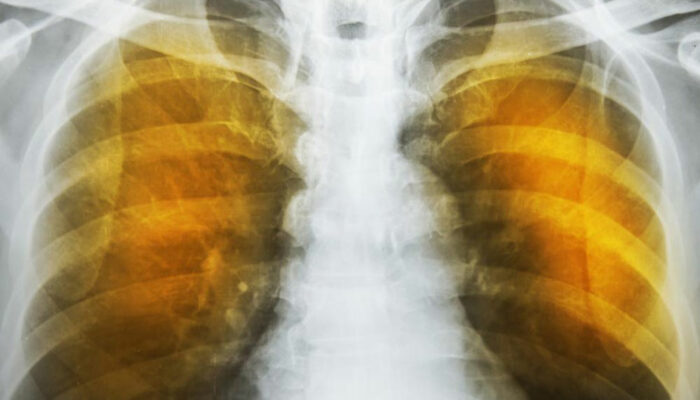

The next reaction is to cough out the irritants and the mucus. Severe forceful coughs can raise the pressure in the alveoli considerably and can rupture their exceedingly thin walls. The reduction of area for gas transfer and the loss of elastic tissues in the lungs reduces the capacity of the lungs to expel air. This reduces the intake volume of fresh air during breathing and can also lead to infections. These conditions produce the characteristic symptoms of wheezing, tightness in chest, labored breathing and coughing. These are also indications as well as symptoms of severe asthma.

As the deterioration continues, the alveoli lose their strength and start rupturing. In extreme cases, there may be large scale destruction which leads to empty spaces in lungs called bullae. This would reduce the functional area of the lung which in extreme cases call for surgical removal. In an extremely rare condition, large scale rupture of alveoli can cause a condition called pneumothorax and the collapse of the lung, a very serious condition, which can be fatal. The best thing one can do is stop exposure to irritants.